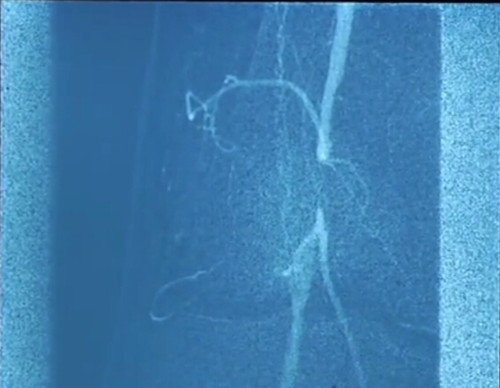

粥样斑块切除术治疗周围血管损伤

粥样斑块

周围血管损伤